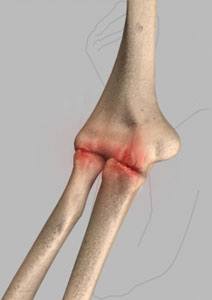

Elbow Fractures

Elbow fractures may occur from trauma, resulting from various reasons: a fall on an outstretched arm, a direct blow to the elbow...